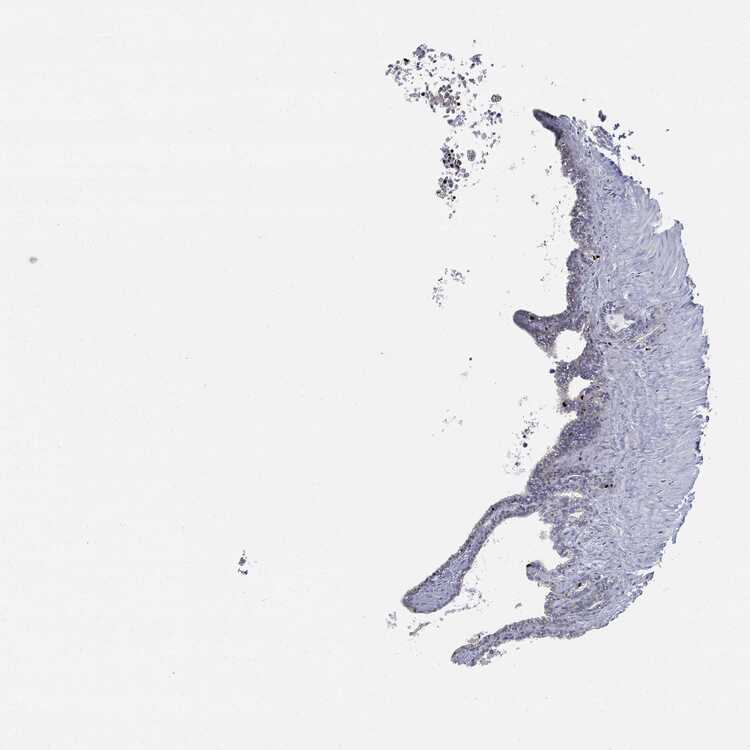

TISSUE PRIMARY DATA SEMINAL VESICLE Show tissue menu

SEMINAL VESICLE - Antibody stainingi

Antibody staining in the annotated cell types in the current human tissue is reported as not detected, low, medium, or high, based on conventional immunohistochemistry profiling in selected tissues. This score is based on the combination of the staining intensity and fraction of stained cells.

Each image is clickable and will lead to virtual microscopy that enables deeper exploration of all samples and also displays staining intensity scores, fraction scores and subcellular localization as well as patient and tissue information for each sample.

Antibody HPA000451Antibody HPA001164Antibody CAB000058Antibody CAB068198Antibody CAB080228

Glandular cells Not detectedHighLowNot detectedNot detected